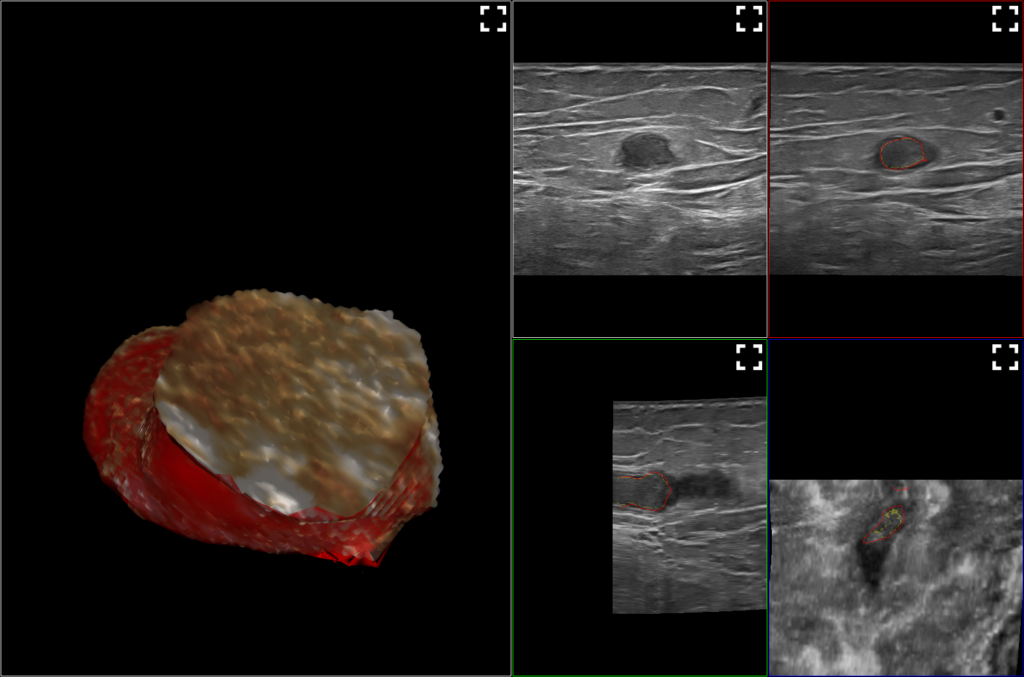

Imagerie 3D

L’image 3D permet notamment de choisir le point d’injection le plus adapté pour favoriser l’obtention de ce veinospasme prédictif d’un bon résultat.

Sclérothérapie échoguidée à la mousse : nouveaux horizons ouverts par la 3D. Ultrasound Guided sclerotherapy with foam: new horizons open by 3 D.

Mots-clés : Echo, Mousse, Trois dimensions (3D) ou tridimensionnel

Keywords: Ultrasound, Foam, Three-dimensional (3D) or three-dimensional

3D and Smart Foam, new avenues to explore, to improve the safety and effectiveness of ultrasound guided foam sclerotherapy